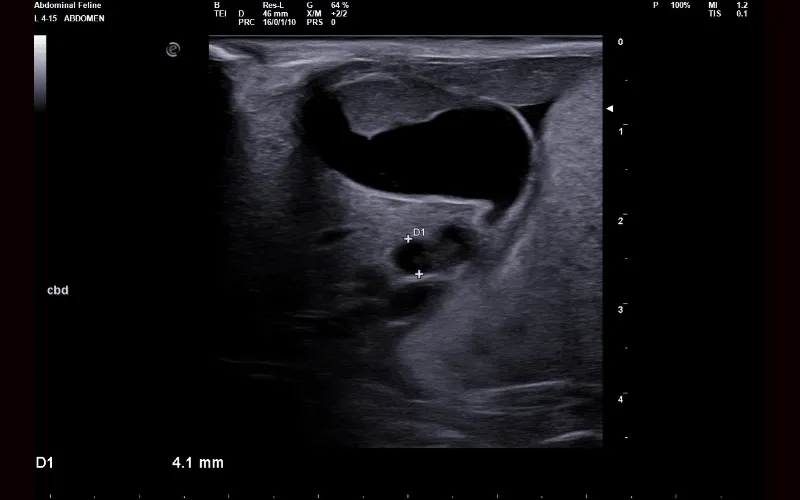

Different diseases and conditions create distinct patterns that become recognisable on ultrasound, even when physical examination or lab work has been inconclusive. Some findings are diagnostic in themselves, while others provide a strong indication of what is developing and the urgency with which it needs to be addressed.

Gallbladder and biliary system

Ultrasound allows us to examine internal organs without surgery. It helps identify changes in tissue structure and assess how organs interact with each other.

Ultrasound can evaluate abdominal organs, soft tissues and other internal structures. This imaging technique helps us look for abnormalities that may affect a cat’s health.

Ultrasound findings can clarify whether disease is localised or affecting multiple organs. This information helps us determine the most appropriate next steps for diagnosis or treatment.